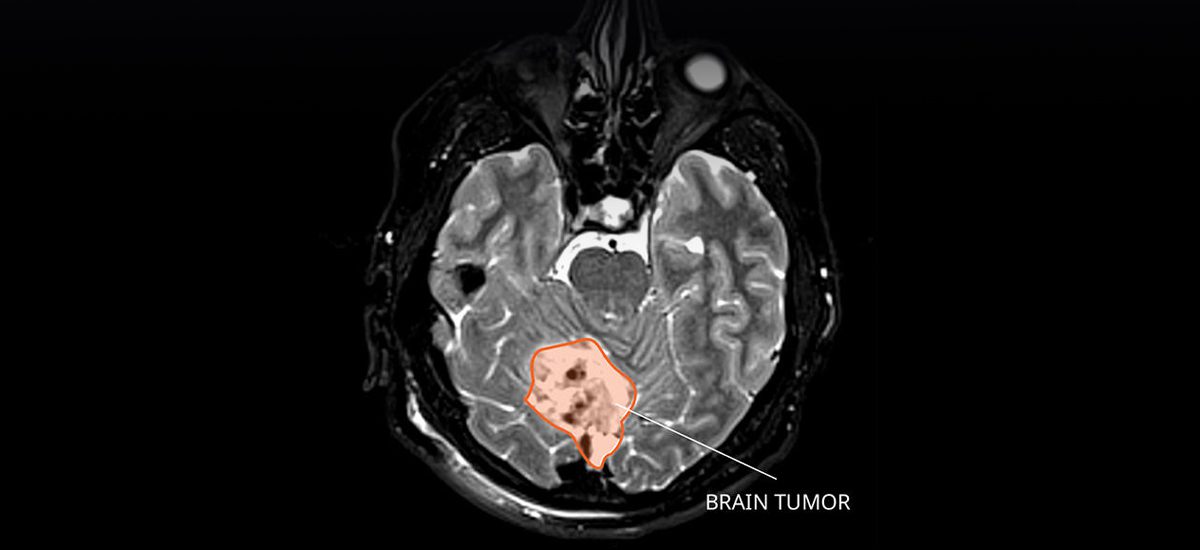

Childhood IllnessWhat is Medulloblastoma? A pediatric neuro-oncologist explains the rare type of cancerous brain tumor, why it is more common in children, and the options for treatment. 6 min read January 12, 2024

Brain TumorA New Approach for Treating Glioblastoma A neurosurgeon explains how a new device could transform treatment for patients with glioblastoma and other malignant brain cancers. 7 min read July 18, 2023